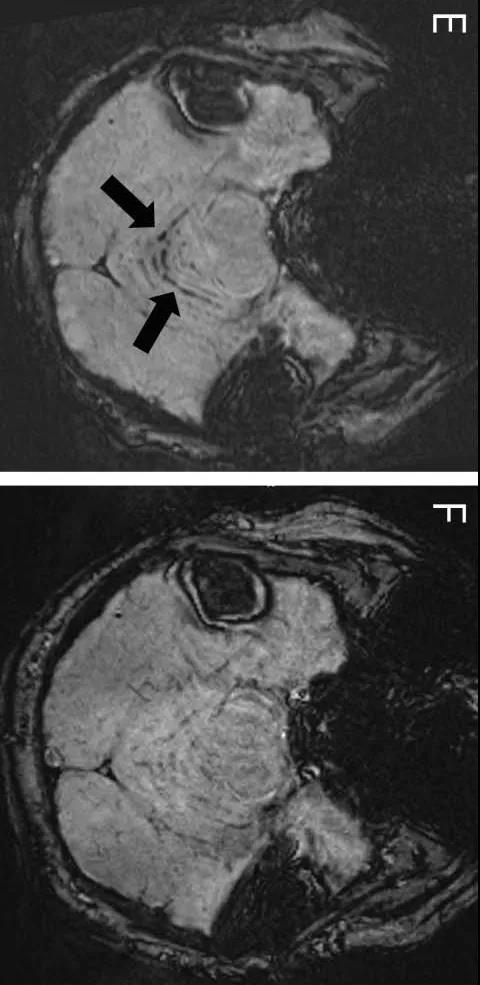

在脊髓CSF渗漏发作5年后获得的轴向SWI显示小脑上部SS(E,箭头),手术后3年和10个月复查轴位SWI显示SS 明显减轻(F):